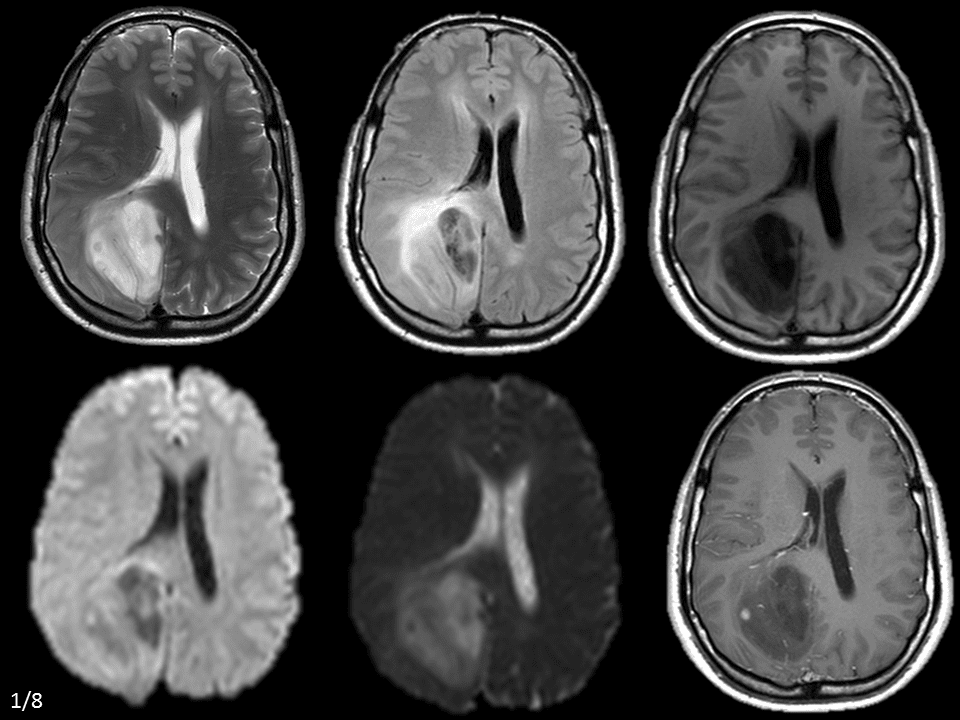

U tế bào hình sao

» Thông tin: Nam giới – 42 tuổi.

» Lâm sàng: Đau đầu.

# U sao bào kém biệt hóa (Anaplastic Astrocytoma)